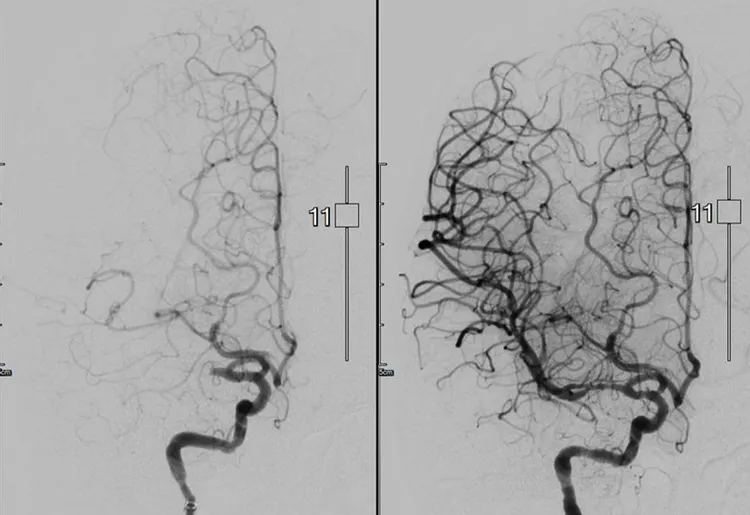

北醫附醫動脈取栓團隊成功吸出出血栓並打通血管。圖為腦血管打通前(左圖)後(右圖)比較。北醫附醫提供

北醫附醫腦中風治療團隊每年啟動約100次,進行動脈取栓治療,血管打通率達 80%以上。北醫附醫提供

北醫附醫影像醫學部鄭碩仁主任表示,與心肌梗塞相比,缺血性腦中風雖然立即性死亡風險較低,但治療速度會直接影響病人預後。以腦部取栓來說,應盡量在2小時內完成,手術時間越長,風險越高,病人預後也越差。